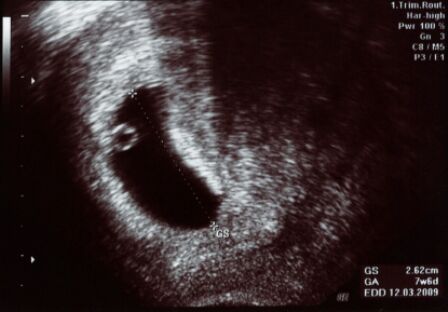

During your menstrual cycle, your body goes through a process that gets your uterus ready to take care of a fertilized egg and make it a nurturing environment to a fetus. If no fertilized egg enters the uterus, your menstrual period begins and the uterine lining that your body has worked so hard to make is shed. However, when fertilization occurs, the blastocyst makes its home in the uterine lining made of blood and tissue, burrowing itself into the lining until it is securely attached. This can cause some discomfort and abdominal cramping. While the egg implants, a piece of lining may separate to make room. This is nothing to be alarmed about and is perfectly normal. The blood or tissue that falls off the uterine lining then makes its way out in the form of implantation bleeding.